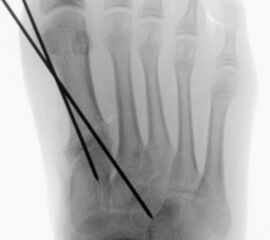

Abb. 26 a-e: adduzierende Osteotomie. (a) Fuß präoperativ d.p. und (b) als Schrägaufnahme. Im Schrägbild gut sichtbar die subluxierte 5. Zehe. (c) intraoperative Aufnahme der MT V Schaftosteotomie. (d) Fuß postoperativ d.p. und (e) als Schrägaufnahme.

Dementsprechend führen wir die MT V Osteotomie häufig als Kombinationseingriff durch. Sie kann subcapital im Sinne der Kramer-Osteotomie oder adduzierend am Schaft durchgeführt werden (Abb. 26).

Liegt eine stark subduktische 5. Zehenposition vor, fräsen wir bevorzugt in der Kramertechnik für eine maximale Korrektur und Setzen für zwei bis drei Wochen einen intramedullären Draht nach proximal durch die Osteotomie (Abb. 27).

Abb. 27 a-d: Radiologische Darstellung intraoperativ (a) und vor dem Entfernen des Drahtes einer kompletten Schaftosteotomie mit intramedullärem Draht stabilisiert (b). Die Osteotomie wird minimalinvasiv durchgeführt und der Draht nach der Spülung über den gleichen Hautschnitt einfach in den Schaft hineingeschoben und die Osteotomie darüber stabilisiert. Das Köpfchen kann anschließend je nach Bedarf plantarisiert oder extendiert werden. Radiologische Verlaufskontrolle vor Entfernung des Drahtes (c-d).